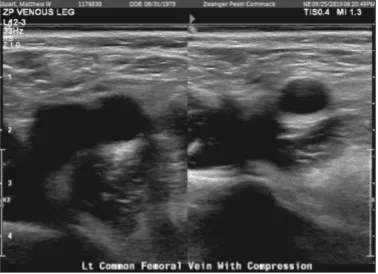

Doppler venous left lower extremity

There are findings consistent with deep vein thrombosis of the left leg. Specifically, there are findings consistent with deep vein thrombosis involving the visualized posterior tibial venous system. The appearance is consistent with acute deep vein thrombosis.